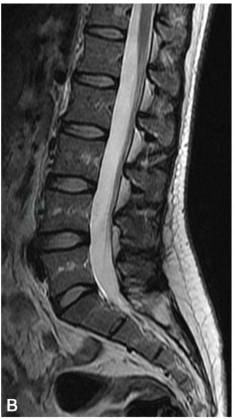

矢状位:显示椎体的连续解剖结构,腰椎呈生理曲度前凸,骶尾椎呈生理性后凸。腰椎椎体呈矩形,椎体边缘骨皮质在T1WI和T2WI上均呈低信号;椎体内随着年龄增长,逐渐由红骨髓向黄骨髓转换,儿童时期主要为红骨髓,T1WI呈低信号,T2WI呈中等信号,随着年龄的增长,椎体内大量脂类或脂肪成分堆积可形成局灶或弥漫性脂肪沉积改变,T1WI呈略高信号,T2WI呈中等信号(图2)。椎体后缘的中间部位有短的条状凹陷,为椎基静脉所致。椎体的附件包括椎弓、椎弓根、椎板、棘突、横突及上、下关节突等,其信号与椎体的信号类似。

图2 正常腰椎MRI图像

A.T1WI;B.T2WI;C.T2WI 脂肪抑制序列椎体松质骨呈中等信号,皮质骨呈低信号,椎体内脂肪沉积呈高信号,脂肪抑制序列呈低信号,脑脊液呈T1为低信号,T2为高信号